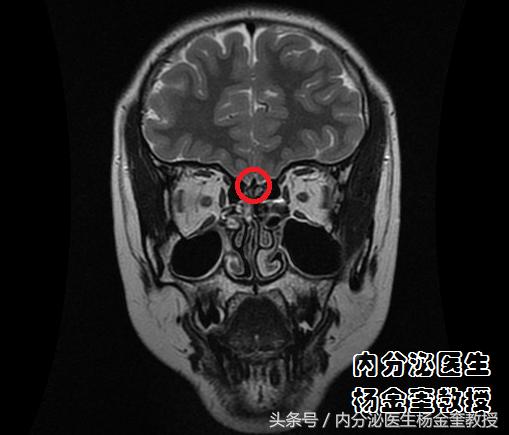

图片中,核磁检查显示恼的『嗅觉』中枢,嗅球不发育。

图片中,核磁检查报告,双侧嗅球非常小。